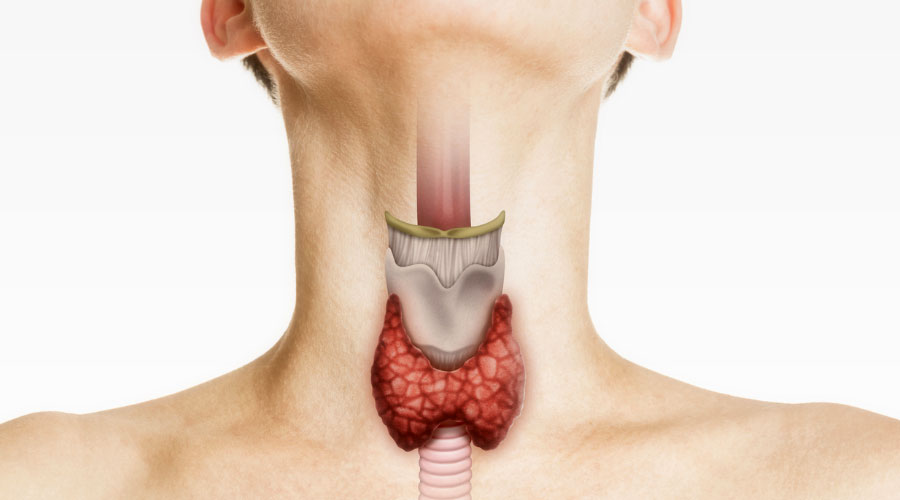

La thyroïde peut être augmentée de volume avec ou sans irrégularités . Située à l’avant du cou, la thyroïde est une petite glande contrôlée par l'hypophyse. Le sélénium protège aussi la thyroïde de l’inflammation, notamment lorsque des maladies auto-immunes l’attaquent.

Le carbimazole, médicament très utilisé en Europe, est converti en méthimazole dans l’organisme. Page 1 sur 1: Poster un nouveau sujet: Auteur Message; tender. En pratique : Devant la fréquence des dysthyroïdies (4% à 25%) : Doser la TSH trimestriellement puis . Elle fabrique deux types d’hormones – la T3 et la T4 – qui tout à la fois régulent le métabolisme des cellules de notre corps ; contrôlent l’énergie musculaire, l’humeur et la température du corps ; augmentent le rythme .Le centre de référence des maladies rares de la réceptivité hormonale a été sollicité à plusieurs reprises, et de nombreux cliniciens ont été interpellés pour des bilans .Le diagnostic de l’hypothyroïdie est le plus souvent établi par le médecin traitant, en collaboration avec des médecins spécialistes (endocrinologue, radiologue. Elle est constituée de deux lobes, de part et d’autre du larynx. Ils diminuent la production d’hormones par la thyroïde. Lors de l’utilisation des hormones thyroïdiennes, une petite partie de leur iode est libérée et retourne à la thyroïde où elle est réutilisée pour fabriquer d’autres hormones thyroïdiennes. Sa forme est celle d'un papillon dont les deux ailes (les lobes) sont symétriques, et situées contre les . La maladie disparaît généralement spontanément . Cortisone et soleil.

Une suractivité anormale de la thyroïde entraîne, elle, de la nervosité, des sautes d’humeur, de l’insomnie, une transpiration excessive ou encore de la tachycardie.Tous ces maux caractérisent une hypothyroïdie. Réguler la température du corps, son poids, sa force musculaire. En cas d'hyperthyroïdie avec saillie des globes oculaires (maladie de Basedow le plus souvent), un traitement médical est d'abord tenté, en administrant pendant 18 mois un médicament capable de freiner l'activité de la glande. Contrôler la pression artérielle et le rythme cardiaque. Des molécules proches des hormones naturelles. Il palpe le cou.Un dérèglement thyroïdien se caractérise par un fonctionnement anormal de la thyroïde, une glande située à la base du cou.La thyroïde est une glande située en bas du cou, se présentant sous forme de deux lobes, à l’image de deux ailes d’un papillon, reliées par un isthme. Toutefois, si vous utilisez une approche méthodique et comprenez la signification de chaque test, vous saurez si vous avez ou non un problème de thyroïde et, le cas échéant, de quoi il s'agit.Il existe deux hormones thyroïdiennes : T4 : Thyroxine (également appelée tétraiodothyronine) T3 : Triiodothyronine. Localisation de la thyroïde.L’iode est un nutriment crucial pour le bon fonctionnement de notre glande thyroïde.La thyroïde est une glande située en dessous de la pomme Adam, dans la partie antérieure du cou.

agit en synergie avec les hormones thyroïdiennes au niveau des récepteurs cellulaires. Découvrez en quoi consiste l’hyperthyroïdie. La glande thyroïde, située dans le cou devant la trachée, pèse environ 30 g quand il n'existe pas de pathologies associées, et sécrète des hormones thyroïdiennes sous l'action d'une hormone hypophysaire : la thyréostimuline (TSH).06 décembre 2023.

Présentation de la thyroïde